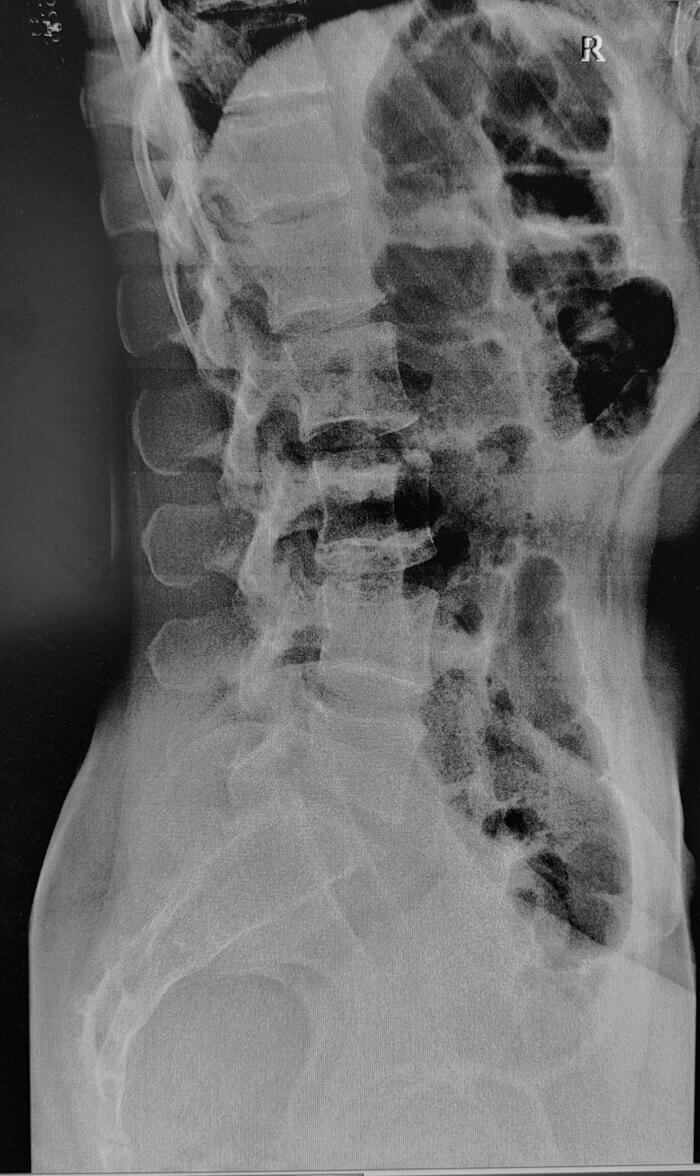

Сакроилиит — это воспаление одного или обоих крестцово-подвздошных суставов. Рентгенограммы поясничного отдела позвоночника пациента с длительным, выраженным болевым синдромом(6 мес.) в пояснице, с временным эффектом от приема НПВС. При описании снимков выраженной костной патологии в поясничном отделе позвоночника не выявлено: структура тел позвонков не изменена, травматических, деструктивных изменений не выявлено, субхондральный склероз замыкательных пластин тел позвонков отсутствует, краевые остеофиты тел позвонков не выявлены, имеется не выраженное неравномерное сужение межпозвонковых щелей как начальное проявления остеохондроза-такая рентгенологическая картина не дает столь выраженного и длительного болевого синдрома. Обращают на себя внимание крестцово-подвздошные сочленения(КПС),отмечается неравномерное не выраженное сужение щелей КПС с локальными участками расширения, субхондральный склероз- более выраженный слева, имеются двусторонние краевые остеофиты, в нижней трети левого К

Рентгенограммы поясничного отдела позвоночника пациента с длительным, выраженным болевым синдромом(6 мес.) в пояснице, с временным эффектом от приема НПВС. При описании снимков выраженной костной патологии в поясничном отделе позвоночника не выявлено: структура тел позвонков не изменена, травматических, деструктивных изменений не выявлено, субхондральный склероз замыкательных пластин тел позвонков отсутствует, краевые остеофиты тел позвонков не выявлены, имеется не выраженное неравномерное сужение межпозвонковых щелей как начальное проявления остеохондроза-такая рентгенологическая картина не дает столь выраженного и длительного болевого синдрома.

Обращают на себя внимание крестцово-подвздошные сочленения(КПС),отмечается неравномерное не выраженное сужение щелей КПС с локальными участками расширения, субхондральный склероз- более выраженный слева, имеются двусторонние краевые остеофиты, в нижней трети левого КПС суставная щель не ровная, "изъеденная", по причине наличия единичных эрозий костной ткани. Заключение: Двусторонний сакроилиит 2 ст.(более выраженный слева).

Рентгенологические градации сакроилиита в соответствии с модифицированными Нью-Йоркскими критериями диагноза англизирующего спондилита:

• 0 стадия - Отсутствие изменений

• 1 стадия - Подозрение на наличие изменений (отсутствие конкретных изменений, смазанность субхондрального слоя).

• 2 стадия - Минимальные изменения (небольшие локальные области с эрозиями или склерозом, сужение или неравномерность суставной щели.)

• 3 стадия - Безусловные изменения (умеренный или значительный сакроилиит с эрозиями, склерозом, расширением, сужением щели или частичным анкилозом)

• 4 стадия - Далеко зашедшие изменения (полный анкилоз)